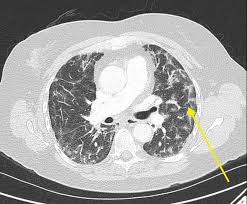

The Stages Of Pulmonary Sarcoidosis What Do They Really Mean Foundation For Sarcoidosis Research from www.stopsarcoidosis.org Lung cancer and pneumonia can, at times, mimic each other on both radiographs and ct. 50 % lung cancer or 50% pneumonia. Won't have the results until july 7th. About 230,000 new cases of lung cancer are diagnosed annually, and about 160,000 lung cancer patients do not survive for more than five years. Diagnostic errors occur frequently in medicine. When sarcoidosis affects the lungs, symptoms can mimic idiopathic pulmonary fibrosis including shortness of breath and a dry cough. It may be more difficult to identify. Lung cancer is sometimes found this way.

Sometimes they will be differentiated by time course, biopsy or other testing. However, bacteria and viruses cause the majority of pneumonia infections. Lung cancer and pneumonia can, at times, mimic each other on both radiographs and ct. Diagnostic skills are fundamental to the practice of medicine, yet misdiagnosis causes death or disability to over 150,000 patients annually. I like you went through breast cancer.